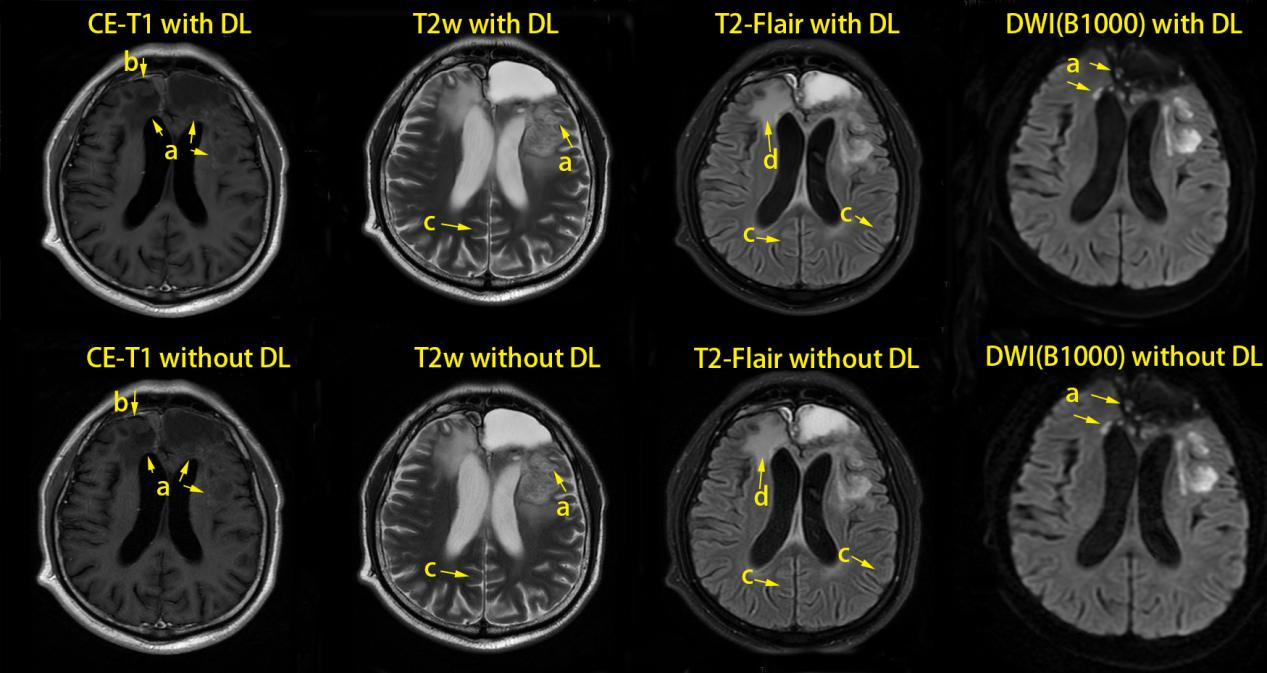

Figure 1 One case’s multi-modal images of DL and conventionally reconstructed (non-DL) methods

The patient was male with age of 39 years.

The mark a and b is lesion, c is artifact, and d is edema.

DL: deep learning